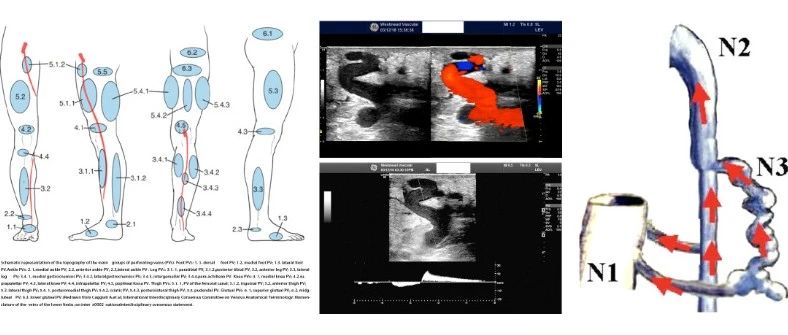

CEC 2022 | 邓建平:非隐静脉来源的下肢静脉曲张

更多精彩内容请到CEC APP “会议日程”观看

CEC 2022 | 杜昕:从血流动力学角度重新认知下肢穿通静脉 --CVI中的原罪?

CEC 2022 | 朱越锋:谨慎处理穿通支静脉

CEC 2022 | 蒋劲松:如何迎接下肢静脉曲张的静脉胶时代?